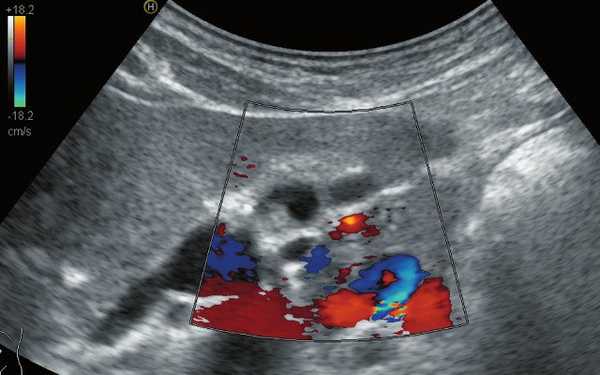

В ложе ближе к шейке желчного пузыря, нечетко дифференцируясь от задней стенки, определяется жидкостная структура с тонкими стенками и однородным содержимым размерами 0,9 х 0,6 х 1,1 см (рис. 2), аваскулярная (рис. 3, 5), не меняющая размеров и формы после пищевой нагрузки (рис. 4). Соустье между описываемой структурой и задней стенкой пузыря визуализируется нечетко.

Рис. 2. Эхограмма дивертикула задней стенки желчного пузыря до пищевой нагрузки.

Рис. 3. Эхограмма желчного пузыря в режиме ЦДК до пищевой нагрузки.

Рис. 4. Эхограмма дивертикула задней стенки желчного пузыря после пищевой нагрузки.

Рис. 5. Эхограмма желчного пузыря в режиме ЦДК после пищевой нагрузки.